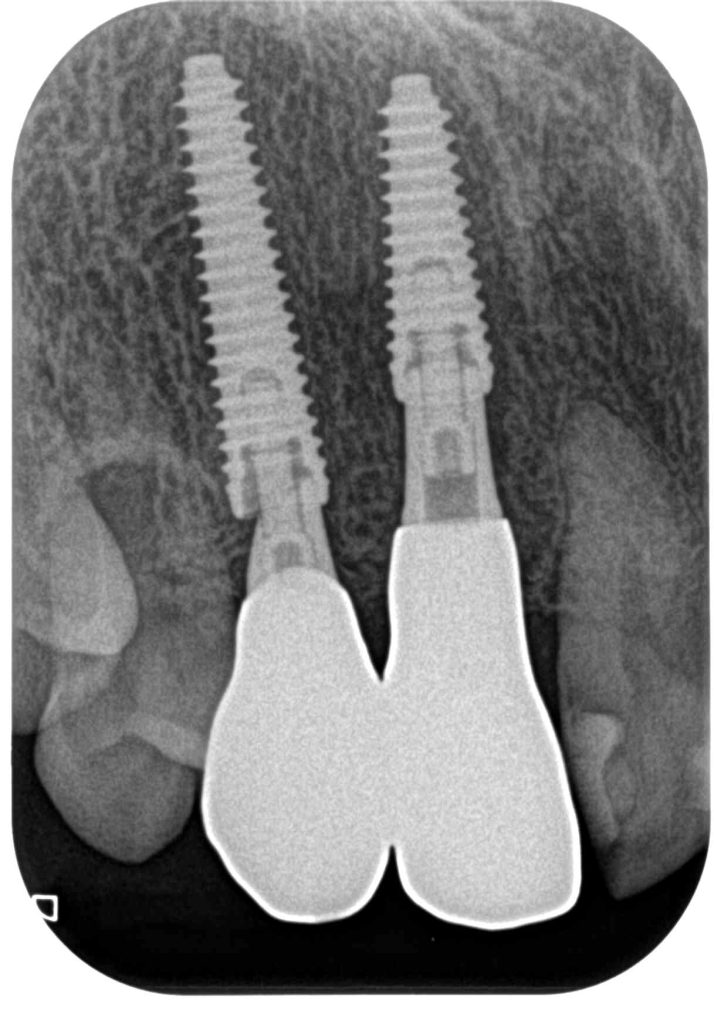

症例330代 女性 前歯のブリッジが動く

治療前

治療後

海外で前歯のブリッジの治療を行うが、4本連結欠損を左右犬歯のみで支える設計の為、力学的に荷重負担となり動揺が生じる状態であった。

従って、左右側切歯にインプラントを2本埋入。生着するまでは、暫間インプラントを立て、審美・機能を果たせるように計画。約2ヶ月の免 荷期間を経て、ジルコニアブリッジを装着。

リスクとしては外科的侵襲がある。デメリットは、保険外診療の為、経済的負担がある。

費用 136万(税込)(オペ・仮歯・最終補綴物まで含む)